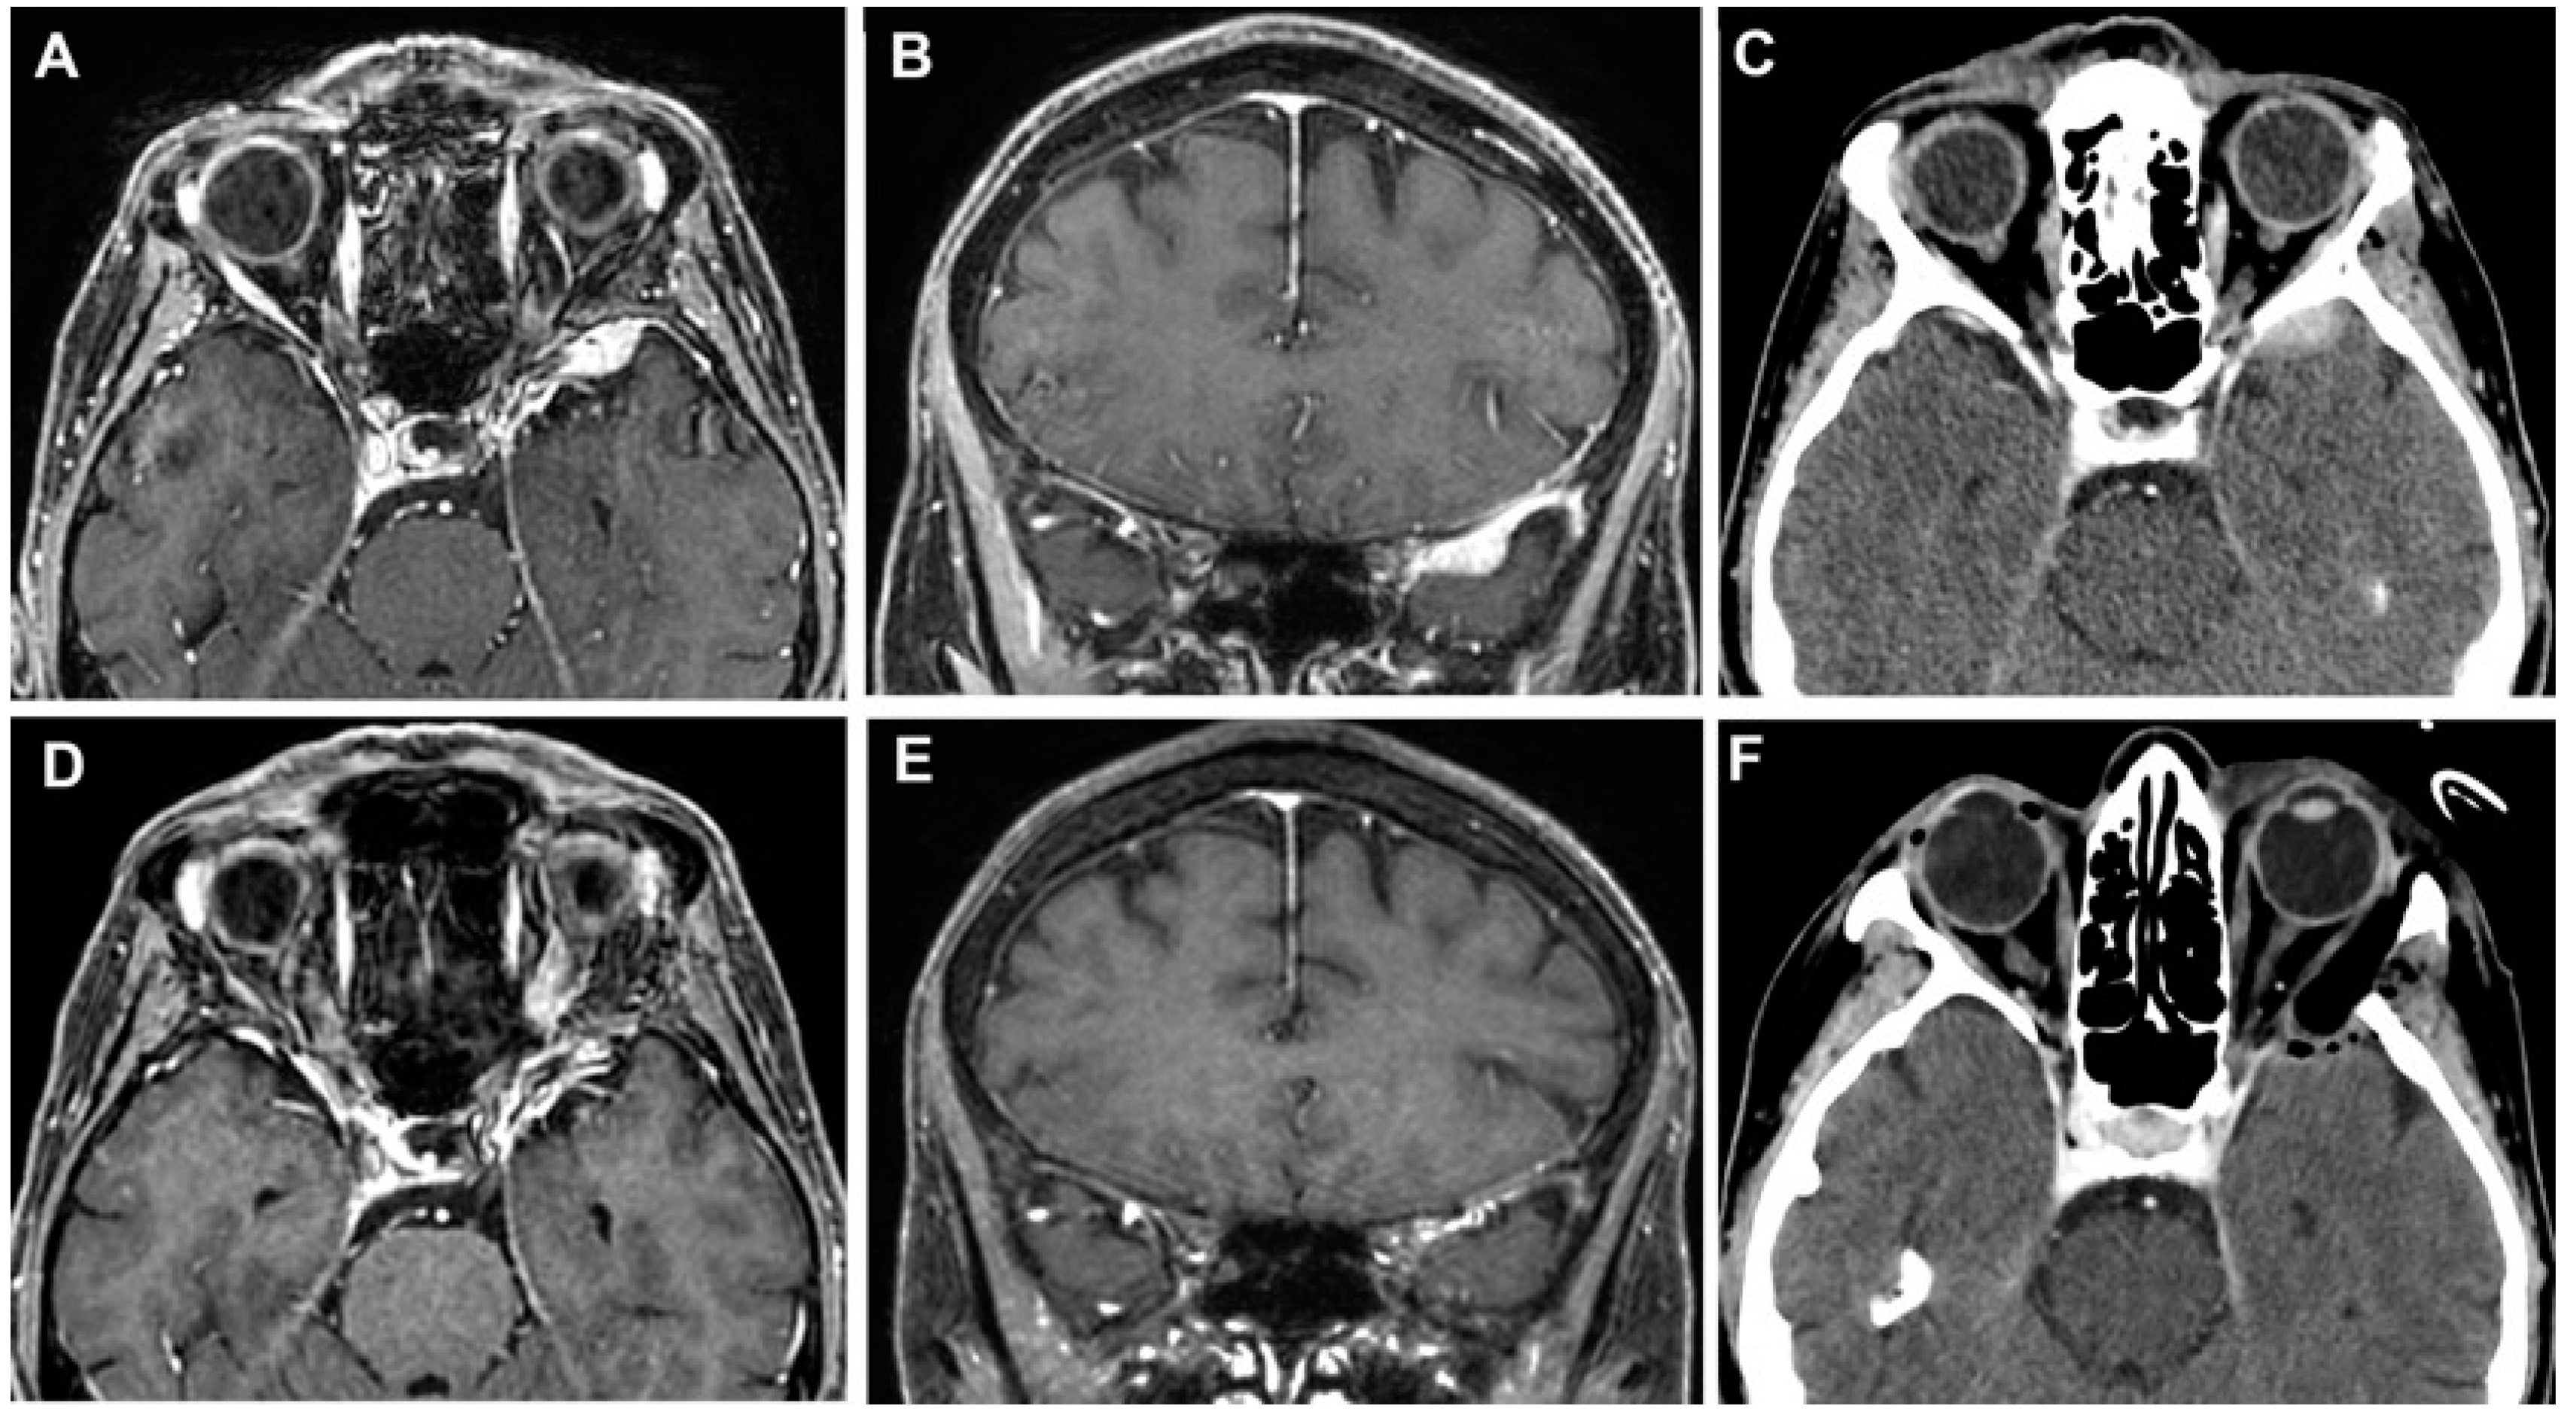

3.3.2. Case 2